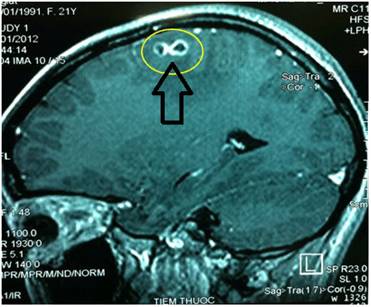

Liên quan đến câu hỏi của bạn ,chúng tôi xin chia sẻ đầy đủ một nội dung liên quan đến test chẩn đoán nhanh phát hiện sốt rét trong nước tiểu. Gần đây, một loại test chẩn đoán nhanh sốt rét trong nước tiểu (The first point-of-need diagnostic for malaria) được xem là một công cụ chẩn đoán sốt rét tức thời đầu tiên.

Hình 21

Test chẩn đoán nhanh sốt rét trong nước tiểu (Urine Malaria Test_UMT) của tập đoàn Fyodor, hiện đang trong quá trình đánh giá lâm sàng, được chỉ định sử dụng cho những người có triệu chứng sốt nghi ngờ do sốt rét. UMT đã được cấp giấy phép sử dụng độc quyền toàn cầu từ Đại học Johns Hopkins, Baltimore, Maryland bao gồm một công nghệ que thử (dipstick) mới rất lý tưởng cho việc chẩn đoán nhanh tức thời sốt rét lâm sàng trong nước tiểu thay cho máu và mang lại những tiến bộ đáng kể hơn nhiều so với chẩn đoán kính hiển vi một khía cạnh nào đó và các công cụ chẩn đoán sốt rét khác đòi hỏi phải sử dụng máu bệnh nhân.

Que thử UMT phát hiện các protein Plasmodium spp. mới xuất hiện trong nước tiểu của những bệnh nhân sốt rét đang có sốt và có thể được tiến hành và đọc kết quả bởi những người được tập huấn ít hoặc không cần tập huấn. Những vệt hoặc các protein mới này không thể bị tách nhỏ ra bởi bất kỳ enzyme protease nào, có thể tạo phản ứng miễn dịch mạnh và gây ra phản ứng miễn dịch sớm, và do đó đóng vai trò là các chỉ báo sớm cho thấy sốt rét lâm sàng.

UMT là một xét nghiệm que thử nhanh dựa trên nguyên lý sắc ký miễn dịch tương đối nhạy và đặc hiệu, có thể dễ dàng tiến hành bởi một người không qua đào tạo với việc sử dụng một mẫu nước tiểu. Để tiến hành, que thử được đưa vào trong một bình hay cốc sạch có chứa 100 µl (5 giọt) nước tiểu, để cho que nhúng ngấm dung dịch khoảng 1-2 phút và ủ trong nhiệt độ phòng trong 20 phút.

Nếu trên que thử xuất hiện hai vạch, thì xét nghiệm là dương tính; nếu chỉ xuất hiện một vạch, thì xét nghiệm là âm tính. UMT cho thấy hiệu quả tương đương so với các test chẩn đoán nhanh sử dụng mẫu máu (RDTs) đang có mặt trên thị trường dùng để chẩn đoán nhanh sốt rét, có giới hạn phát hiện 125 ký sinh trùng/µl, đây là con số khá tốt trong phạm vi hiệu suất phân tích 100-200 kst/µl khuyến nghị đối với các RDTs sốt rét bởi Tổ chức Y tế Thế giới.